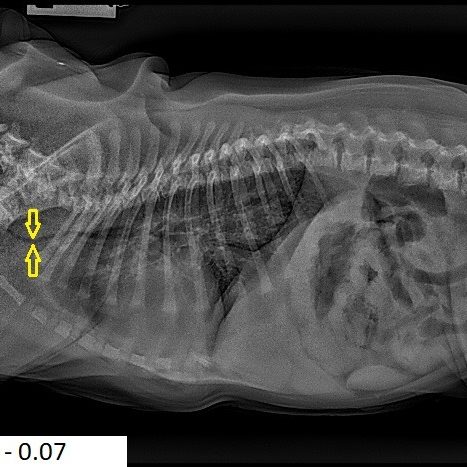

A trachea is considered hypoplastic if it’s ratio is less than 0.16. to 0.20 is a grey area and over 0.20 is excellent. Please see the examples below including Archie who has a normal width of 0.20. Compare the 3 severely hypoplastic ones pictured below.

The three cases discussed/pictured above are extreme. All puppies, all really struggling with bouts of aspiration pneumonia, and all diagnosed with extreme hypoplastic tracheas. Their measurements were 0.07 for two of them and 0.08 for one.